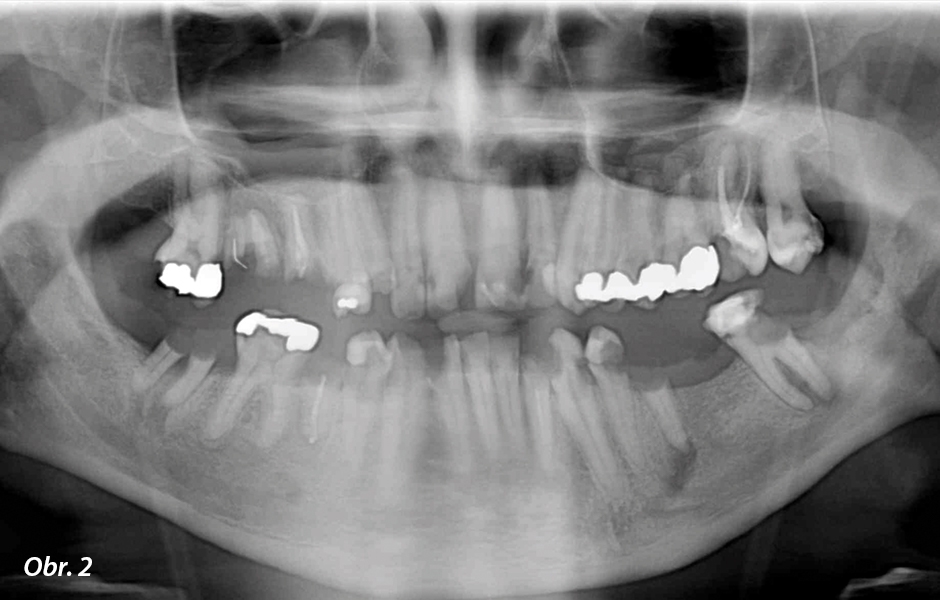

43letý pacient se dostavil ke svému zubnímu lékaři Bjørnu Bortenovi v Melhus Tannhelse, Melhus (Norsko), se závažnými kariézními lézemi ve všech zubech a několika zcela uhnilými zuby (obr. 1a, b, 2). Podle zubního lékaře: „Pacient nebyl v zubní ordinaci více než 15 let. Pacienta, který měl strach ze zubních lékařů a stomatologického ošetření byl problém ošetřit. Trpěl sociální úzkostí, protože neměl zuby. Pracoval na noční směny a přes den zůstával doma. Zjistil jsem, že trpí strachem ze stomatologického ošetření již řadu let, ale nepodařilo se mi od jeho zubního lékaře získat jakoukoli dokumentaci týkající se tohoto strachu, protože sotva kdy nějakého navštěvoval.“ Důvodem, proč se odhodlal překonat strach a vyhledat konzultaci byla nesnesitelná bolest zubů. Jeho prvním přáním bylo vytrhat všechny zuby a zavést implantáty: bolest byla tak silná, že si nemohl čistit zuby a přes zimu jedl kvůli úlevě od bolesti sníh.

Pacient požadoval fixní, bezbolestné, dlouhodobé a jisté řešení, které by mu umožnilo normálně provádět běžné aktivity jako je příjem potravy a čištění. Zubní lékař zase pro pacienta chtěl náhradu, která by se snadno udržovala a kvůli níž by pacient nemusel absolvovat příliš časté kontroly v ordinaci. K ošetření tohoto případu by bylo možné použít několik variant řešení: jako celkové hybridní náhrady, můstky kotvené šroubky nebo kombinace hybridní náhrady a můstku. Pro tento případ však byla nejlepším řešením celková rehabilitace horní a dolní čelisti pomocí zirkonu Prettau® pomocí implantátů, protože fixní rehabilitace byla jediným druhem náhrady, kterou pacient akceptoval. Jako materiál byl zvolen zirkon Prettau® od firmy Zirkonzahn z důvodu jeho dlouhodobé životnosti a schopnosti odolávat ukládání plaku, která by umožnila pacientovi udržovat orální hygienu bez nutnosti odborného čištění v zubní ordinaci.